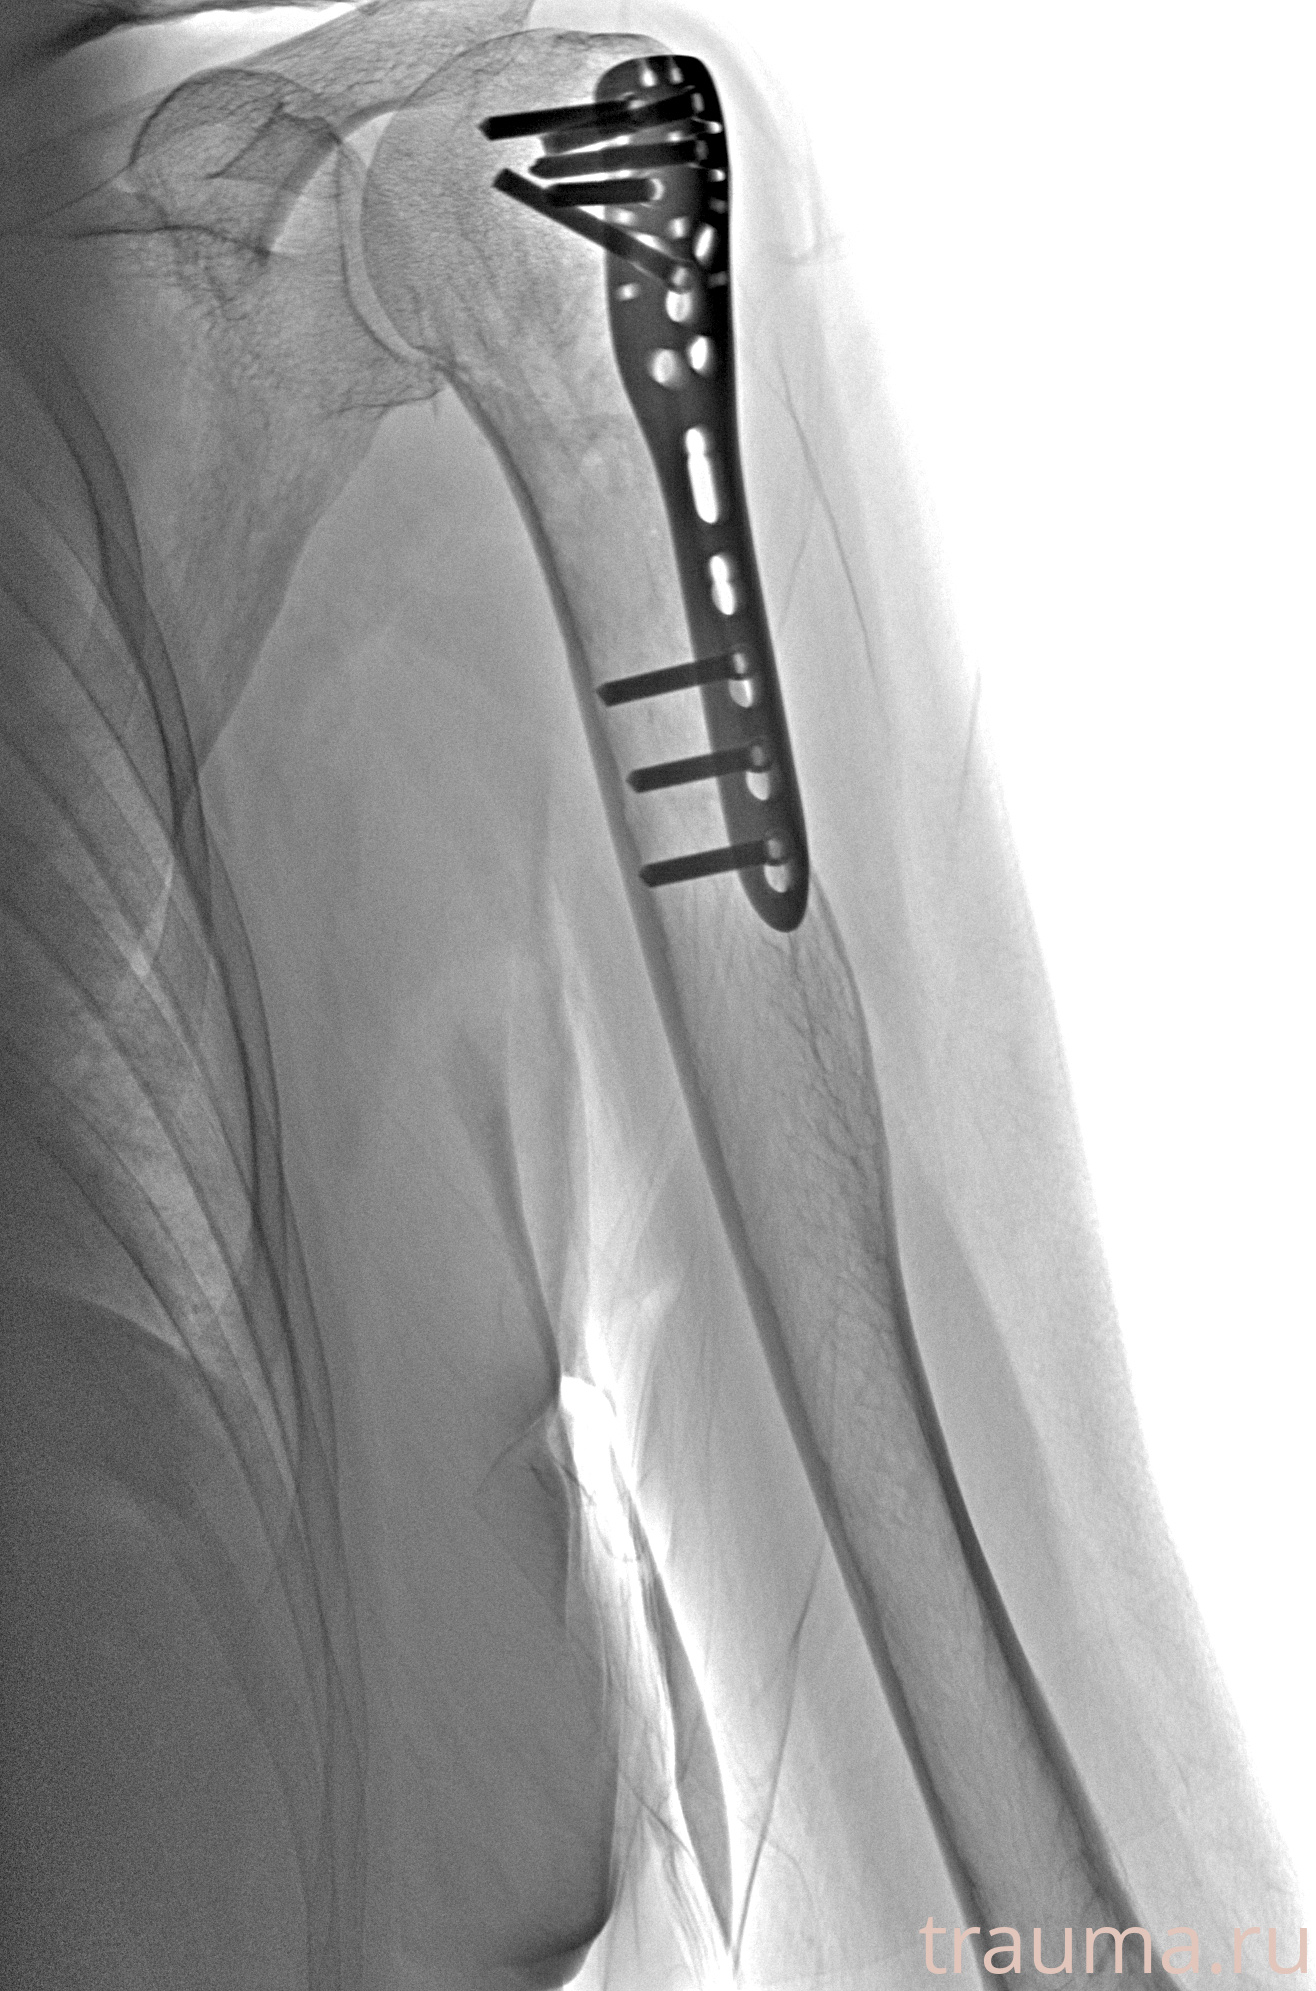

Рентгенограммы